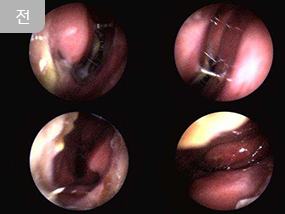

숨쉬는 한의원은 보건복지부 유권 해석에 따라 의료법을 철저히 준수하며, 모든 사진을 게시합니다.

게시된 사진은 실제 숨쉬는 한의원에서 진료받은 환우분의 사례이며, 전후 사진은 동일 환자를 동일 조건에서, 시기만 다르게 촬영하였으며 보정 작업은 일절 하지 않았습니다.

※ 개인별 병력에 따라 치료 기간과 효과는 달라질 수 있습니다.